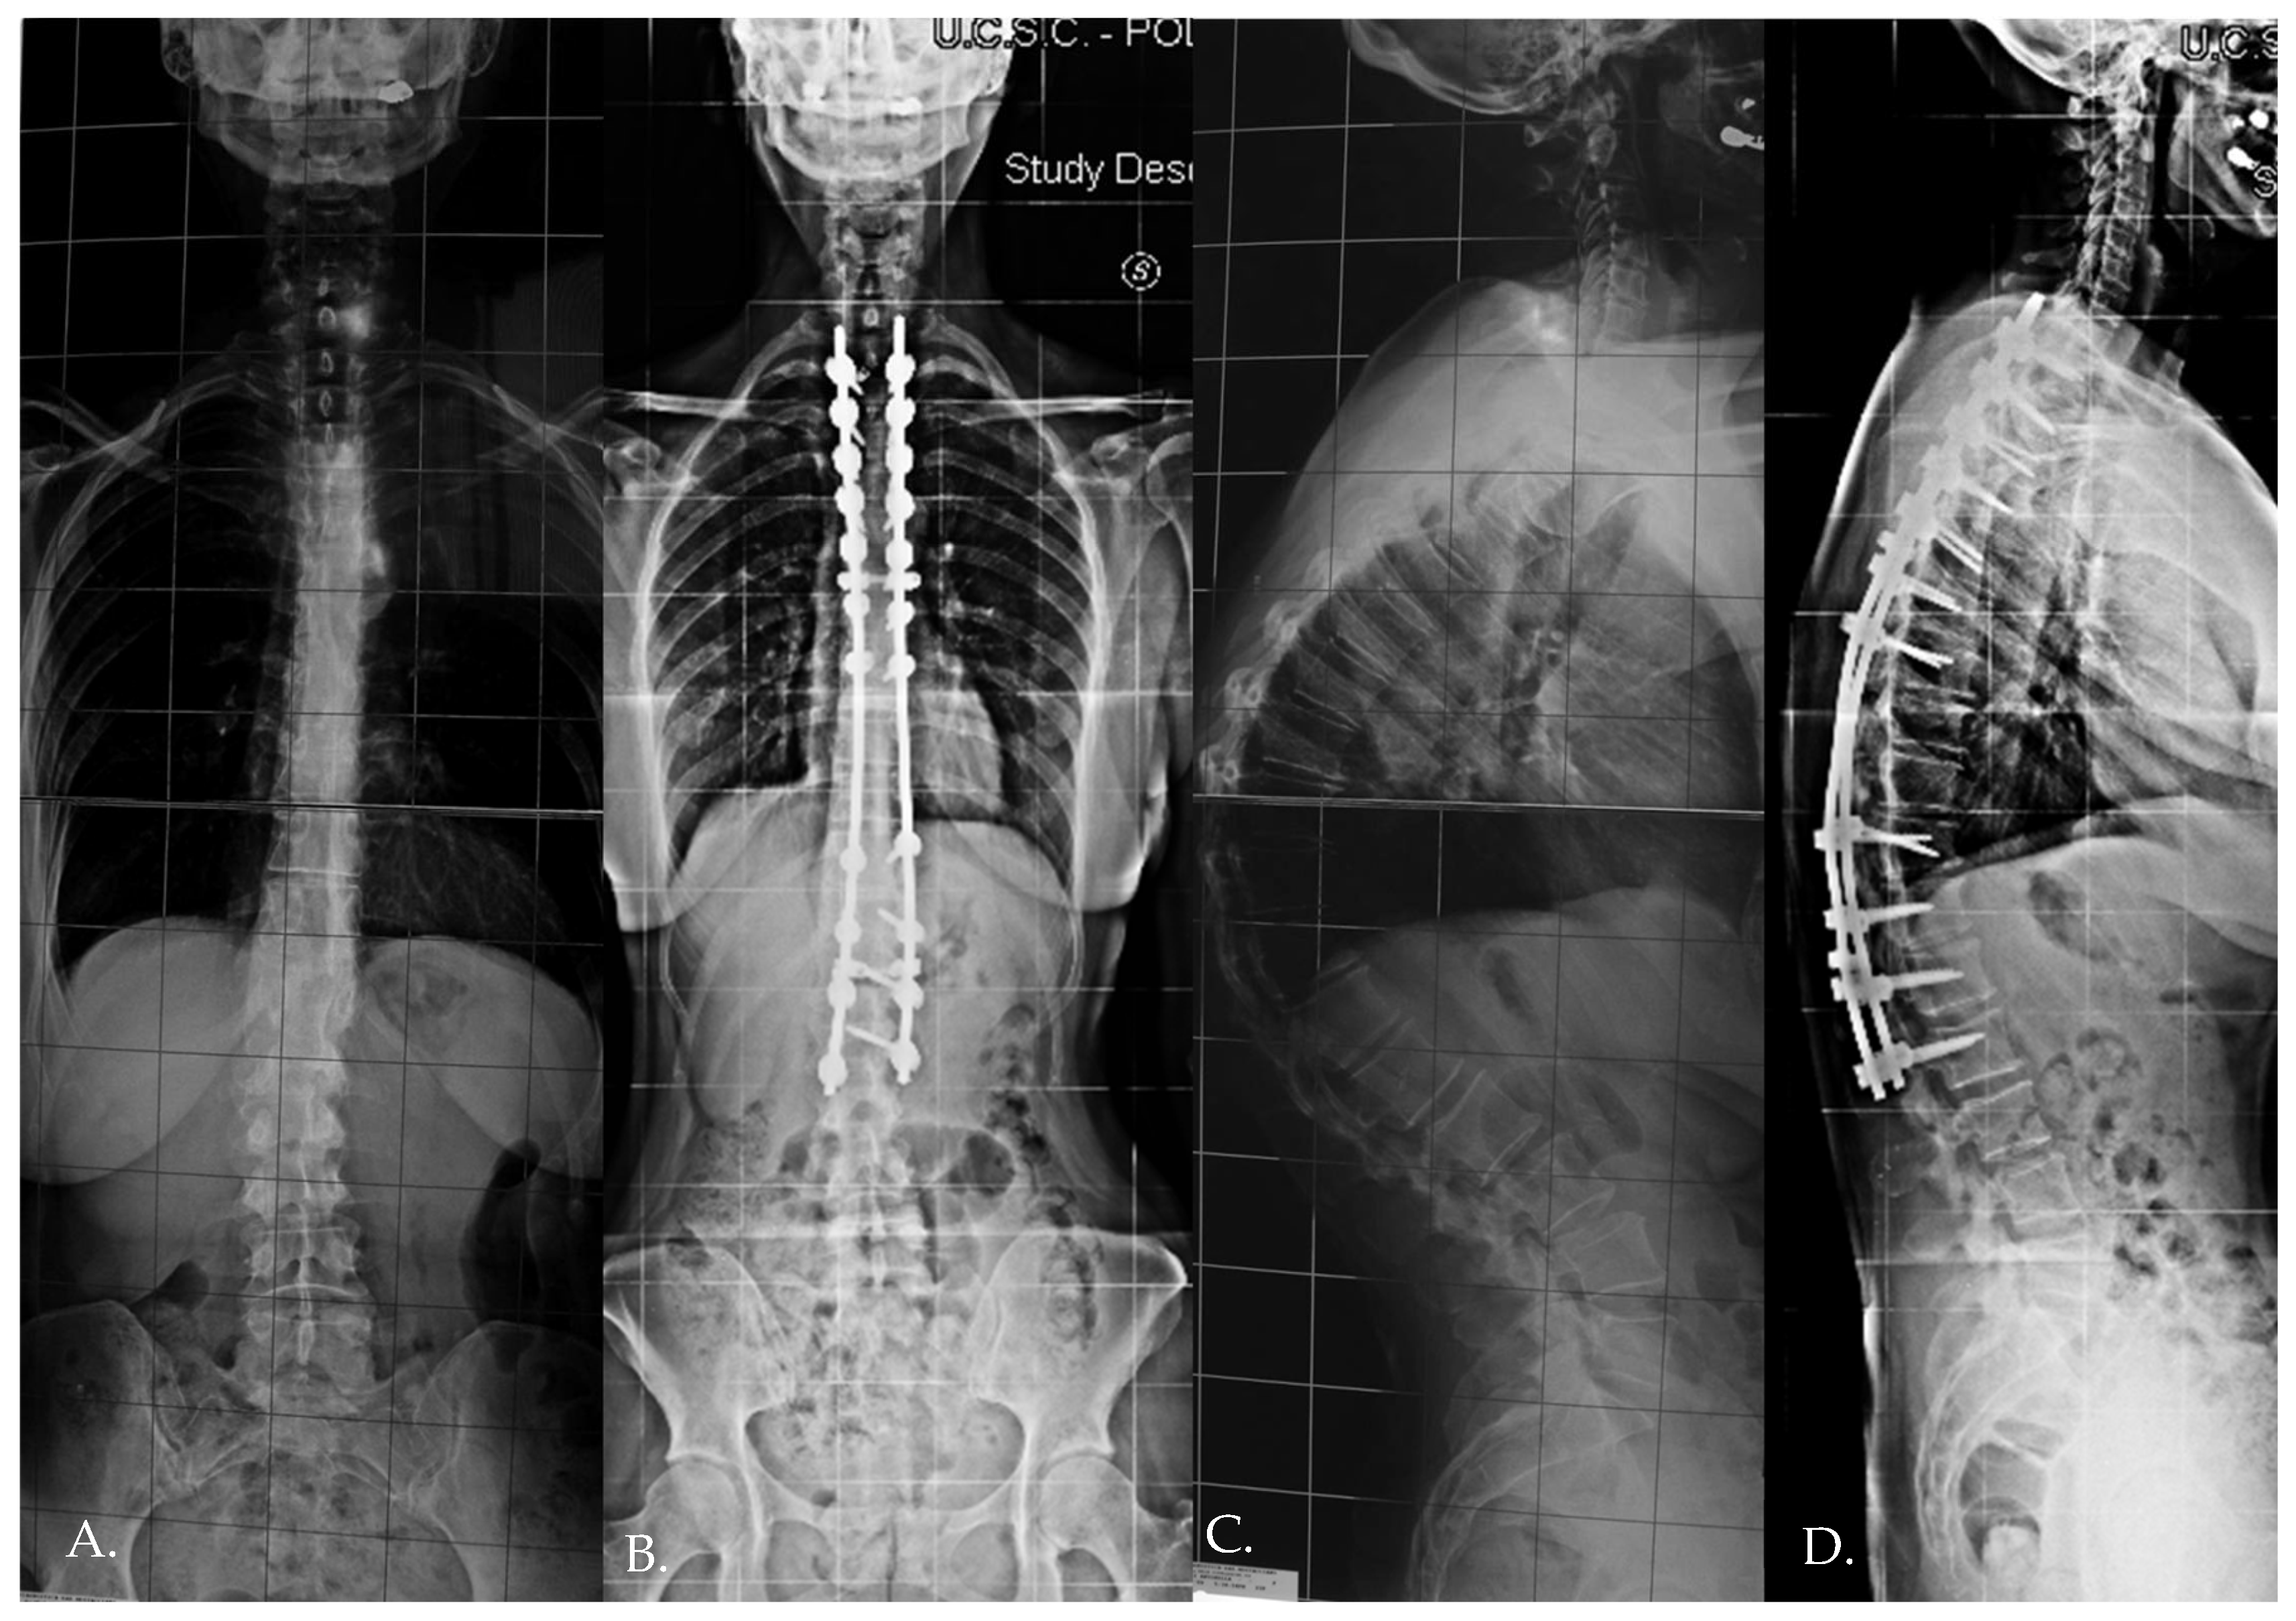

- In Group 1, the mean preoperative DJA was 4.8° (range: 2.2–7.4°), which decreased to 2.2° (range: −7.5° to 6.1°) immediately postoperatively (p = 0.005). At the final follow-up, the DJA was 0.7° (range: −8.3° to 6.1°).

- In Group 2, the mean preoperative DJA was 7.9° (range: 0.2–8.4°), which decreased to 5.6° (range: 0.2–8.5°) immediately postoperatively (p = 0.009). At the final follow-up, the DJA was 4.9° (range: 0.2–7.1°), with a non-statistically significant correction loss of 0.7°.